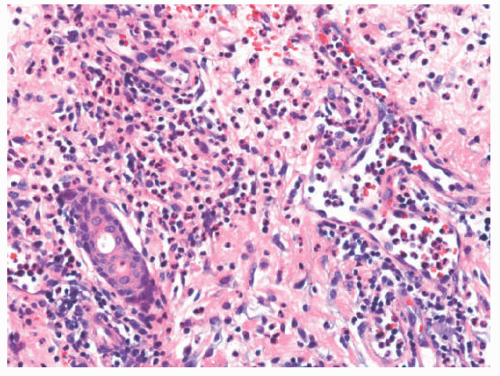

Histologic Findings

Microscopic findings include dense neutrophilic infiltrates in the deep dermis, subcutaneous tissue, and underlying fascia (Figures 17-14 and 17-15). Tissue necrosis and vascular thrombosis are commonly seen, and Weedon defines NF as a form of septic vasculitis.21 Bacteria can be present in sheets, and they may be seen with Hematoxylin and eosin (H&E) stain.